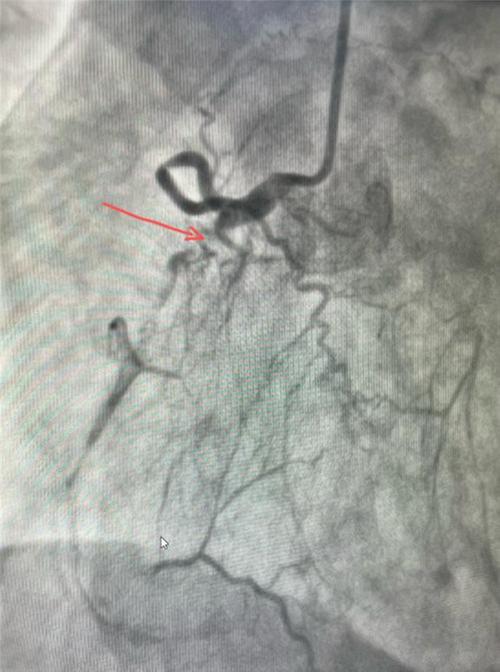

造影图像

患者李某某,一年前出现活动后心累、胸闷、双下肢水肿等情况,在当地医院治疗效果欠佳,病情反复。今年6月15日病情再次加重,到犍为县人民医院心血管内科治疗,经心电图、冠脉造影等检查,显示患者三支血管重度病变,且伴有长节段慢性完全性闭塞,由于患者病情极其复杂,基于医院现有医疗条件,副主任彭宇赓即牵头制定了分级诊疗方案,积极联系四川大学华西医院专家教授,对接住院部优先为患者办理入院,四川大学华西医院成功为患者实施了冠脉手术,及时控制住病情,避免了严重并发症发生。